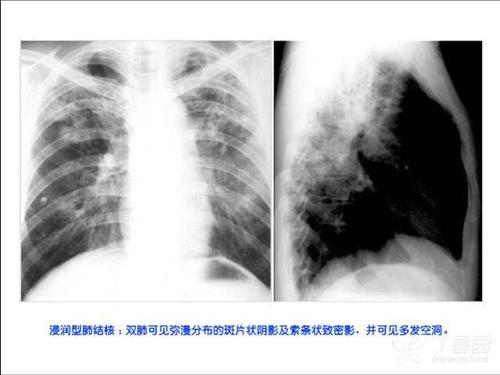

气胸的典型x线表现,气胸的x线表现

图文详解丨气胸的影像学表现